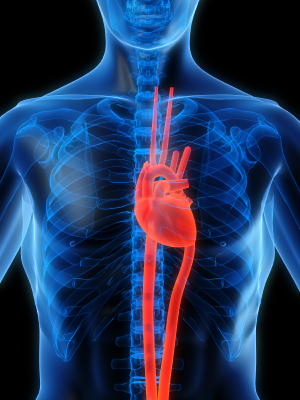

How To Improve Your Heart Health Without Taking Heart Medication With These 7 Proven Steps (from the American Heart Association)

The rhythmic beating of your heart reminds you every day that you are alive, healthy, and well.

However, for some people, the typical beating of the heart may be fluttered, irregular, or very slow.

Not due to anything they did, but due to the medical intervention that may have come about due to a heart attack, stroke, or other condition that may increase the risk of death from cardiovascular disease.

If There Is One Thing You Should Do To Protect Your Heart, It Would Be This